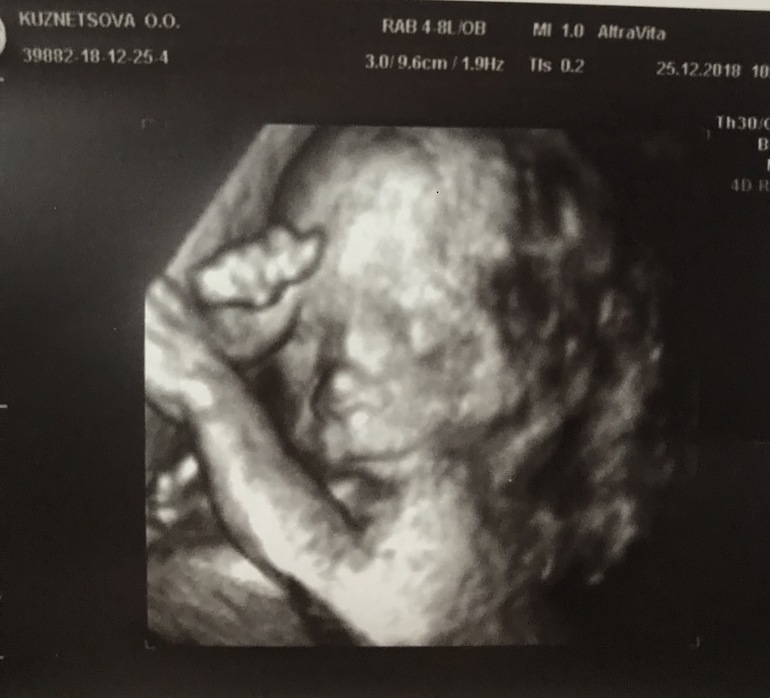

2 скрининг

Сходила к Донову. Все с малышкой хорошо, все соответствует срокам (мозг, сердечко - все отлично), все на месте (и желудок нашли, который другой врач потерял в 16 недель))))

Показали мне длинные пальчики на ручках, худую попу, носик-курносик)))) Вес 388гр (предполагаемый на ПДР 3500гр, но эта инфо, конечно, ни о чем сейчас)

Опережает по срокам немного ❤️